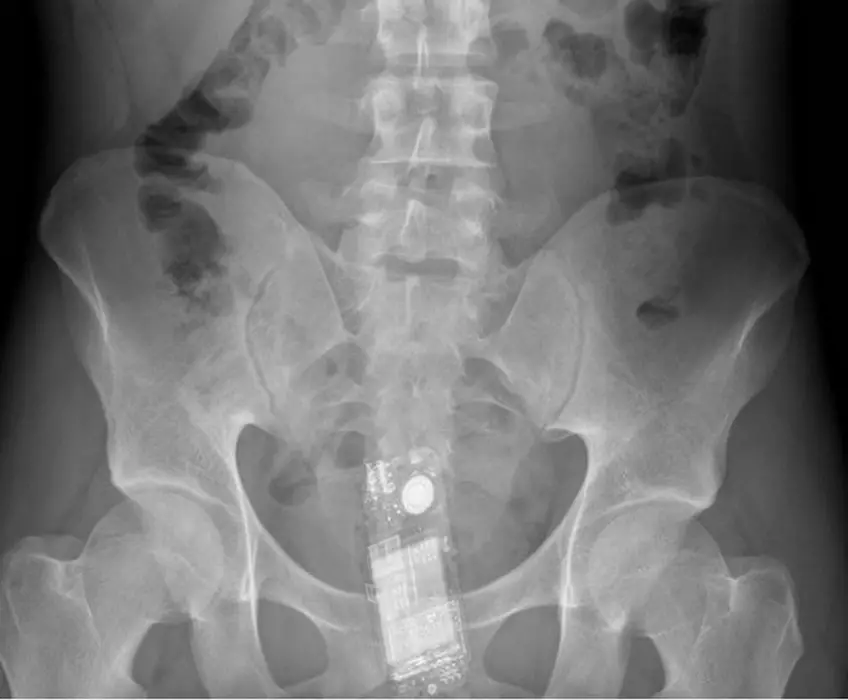

MEDICINA ONLINE OGGETTI CORPO ESTRENEO ANO BAMBINO ESOFAGO STOMACO BATTERIE SEX TOYS OGGETTI SESSO GIOCATTOLI TOSSICI BOTTIGLIA PENNA PENNARELLO COLON RETTO RISCHI COSA FARE COLONSCOPIA

Published 18/04/2018 at 1118 × 924 in Corpi estranei nel tratto digerente: rischi e cosa fare in bambini e adulti

MEDICINA ONLINE OGGETTI CORPO ESTRENEO ANO BAMBINO ESOFAGO STOMACO BATTERIE SEX TOYS OGGETTI SESSO GIOCATTOLI TOSSICI BOTTIGLIA PENNA PENNARELLO COLON RETTO RISCHI COSA FARE COLONSCOPIA INTESTINO DIGERENTE RX RADIOGRAFIA